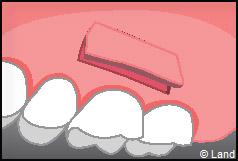

Les greffes de conjonctifs enfouis :

Destinées aux zones esthétiques, elles consistent à prélever la partie profonde du palais (site donneur).

Ce greffon est ensuite inséré sous la gencive au niveau de la récession (site receveur).